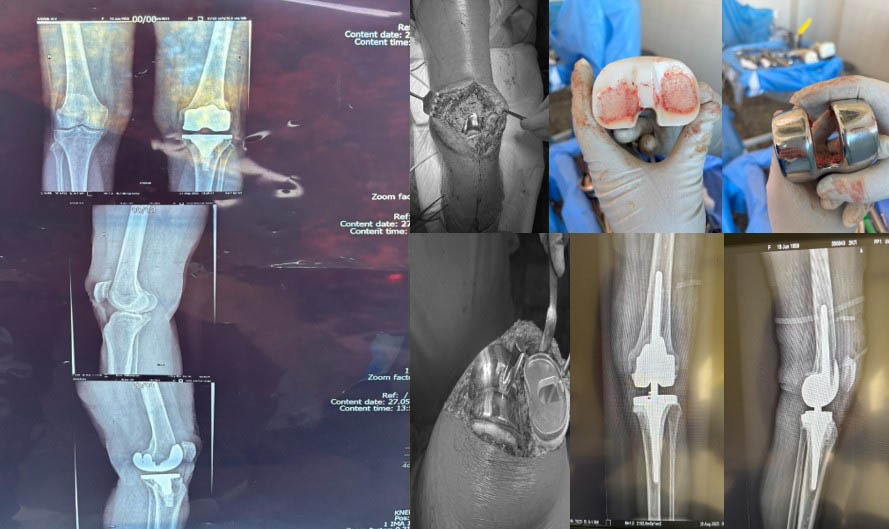

Пацієнтка К.,66 років.Вперше звернулась в ІТО НАМНУ у 2018 році,встановлено діагноз “Лівобічний гонартроз III-IV ст.” Прооперована у тому ж році протезом “CYBORG”.Звернулась повторно на консультацію у травні 2025 року зі скаргами на біль в лівому колінному суглобі.Під час обстеження пацієнтки встановлено асептичну нестабільність компонентів ендопротезу, ФНЕ III ст.

Хвора К.,67 років.У 2020 році виконано ТЕП правого кульшового суглобу у зв’язку з діагнозом “Правобічний коксартроз IV ст.” У січні 2022 року хвора госпіталізована в ВЛШМД з діагнозом “вивих ендопротезу”.Проведена ревізія-заміна ацетабулярного компонента та голівки ніжки ендопротезу. Після оперативного втручання у хворої з’явились ознаки інфекції,утворилась нориця.Пройшла консервативне лікування-ефект відсутній. У березні 2023 році хвора повторно госпіталізується у ВЛШМД з діагнозом “вивих ендопротезу” . Проведена повторна ревізія-заміна ацетабулярного компоненту, пластика цементом та гвинтами. В умовах лабораторії біомедичної інженерії ІТО НАМНУ проведено виготовлення та встановлення індивідуальної ацетабулярної западини.

Паціент М., Міно-вибухове поранення кісток колінного суглобу. Мегадефекти стегнової та Великогомілкової кістки 3 ст по класифікації (Aori). остіоміеліт. Стан після заміщення дефектів спейсером з антибіотиком

Виконане операційне втручання: Видалено спейсери з антибіотиком, резекція за допомогою індивідуальних навігаційних систем та імплантовано ендопротез з індивідуальними аугментами

Проектування та виготовлення індивідуальних аугментів для заміщення дефектів суглобів: М, 48 р, асептична нестабільність онкологічного ендопротеза. Заміщення дефекту індивідуальним аугментом та ревізійним ендопротезом , фіксація БІС, ПММА